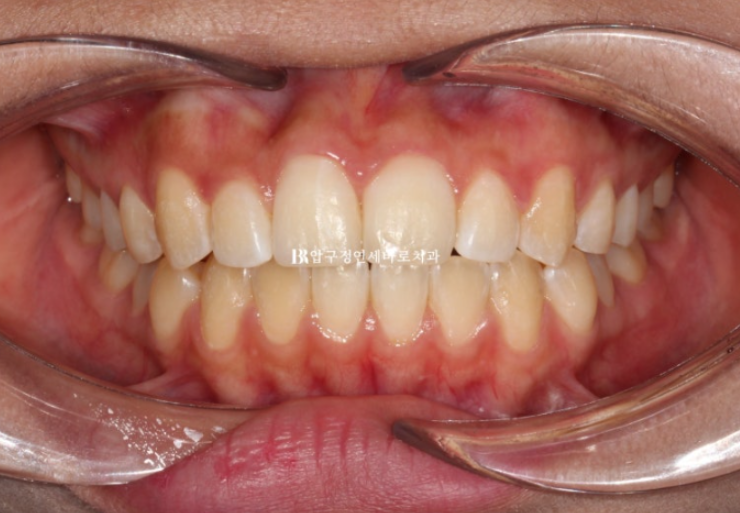

23년 12월 수능 후 환자분이 교정치료를 위해 내원했습니다.

23.12

뻗침도 없고 돌출도 없습니다.

해결하고자 하는 부분은 틀어진 덧니 입니다.

어금니 교합은 나쁘지 않은 편이라 단기 앞니 부분교정을 권유드렸습니다.

앞니 부분교정은 배열 이외에 별다른 기능이 없는 대신 작고 심플한 MTA 미니튜브나 설측 2D 교정장치를 사용합니다.

하지만 이 환자분은 덧니 이외에도 앞니 물리는 것이 얕은 절단교합을 보였기 때문에 앞니 배열 후 고무줄을 걸어 절단교합도 어느정도 해결하기로 했습니다.

따라서 고무줄 거는 기능이 있는 장치 클리피씨를 부착하고 교정을 진행했습니다.